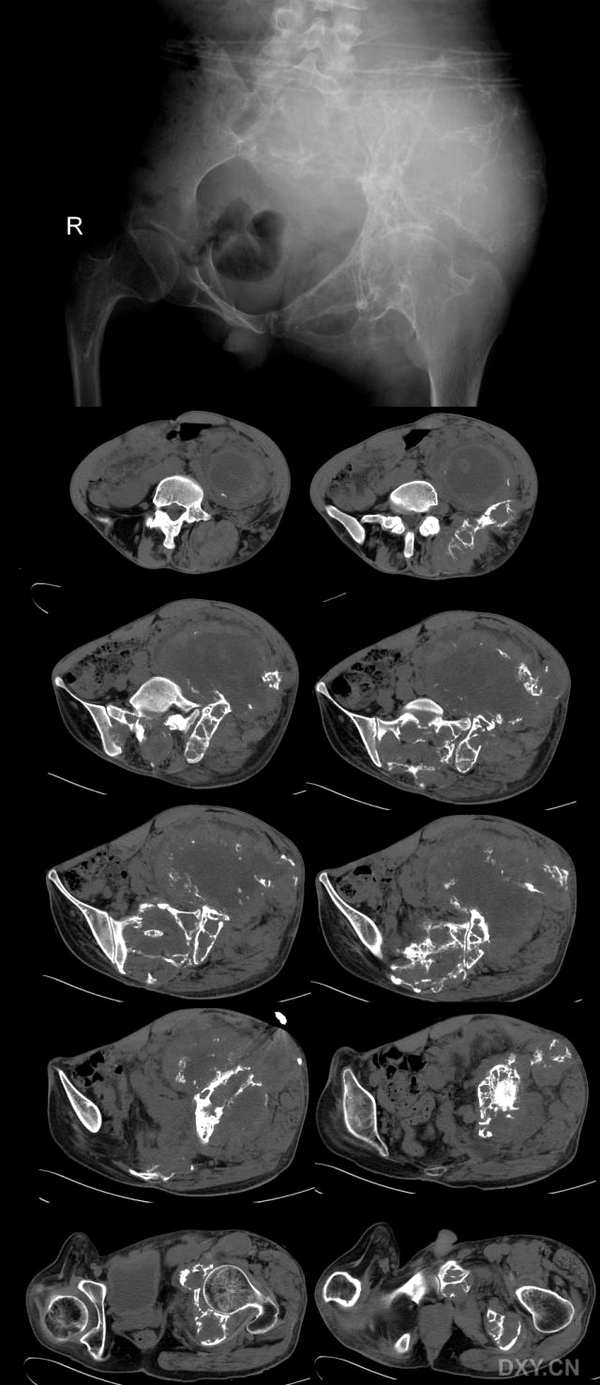

病史:男性,45岁,左髋部疼痛一年余

左侧髂骨见溶骨性股指破坏,边缘模糊,钙化点增多,肿瘤膨胀生长、肿瘤侵入周围软组织中,形成巨大软组织肿块,其内可见散在钙化点。骶骨、左侧髋臼破坏。

意见:软骨肉瘤。

左髂骨溶骨性破坏,边界模糊,肿瘤呈膨胀性生长,可见散在钙化影,并侵犯周围软组织。考虑软骨肉瘤可能性大。

左侧髂骨及骶骨溶骨性破坏,局部形成软组织肿块,以坏死为主夹杂斑点状钙化,残存骨质显示硬化,周围髋部软组织明显肿胀,考虑骶、髂骨结核。

影像表现:左侧髂骨、左侧髋臼及骶骨见溶骨性骨质破坏,其中左髂骨肿瘤呈膨胀性生长,瘤周巨大软组织形成,其内可见散在破坏骨质碎片或钙化点,中间可见液化坏死。

影像诊断:左侧髂骨、左侧髋臼及骶骨恶性骨肿瘤,软骨肉瘤可能性大。

双侧髂骨及骶骨均见溶骨形骨破坏伴软组织肿块,软组织中块内见不规则小的钙化影并可见大范围水样低密度灶。骨质破坏为跳跃性及膨胀性,骨破坏区内及软组织中块内均未见明显环形骨化影(钙化影),软组织肿块对其周围组织推移并可见水肿影。临床提示病程1年。软骨肉瘤不是,因为未见瘤骨及环形软骨钙化影。我考虑骨结核可能性大。

骶骨、左侧髋骨见不规则膨胀性溶骨性破坏;肿瘤侵入周围软组织中,累及盆壁肌及左侧脊竖肌,形成巨大软组织肿块;中央呈低密度,周围呈软组织密度,内见多发小的残存碎骨片;增强后软组织呈轻度强化,中央低密度无强化。

病史:男性,45岁,左髋部疼痛一年余。

影像特点:

1、骨盆多处扁平骨溶骨性破坏并累及左侧股骨上段,无肿瘤骨及钙化;

2、形成巨大软组织肿块;

3、骨破坏区有不规则骨性分隔。

4、临床:男性,45岁,表现左髂部疼痛、肿块一年。